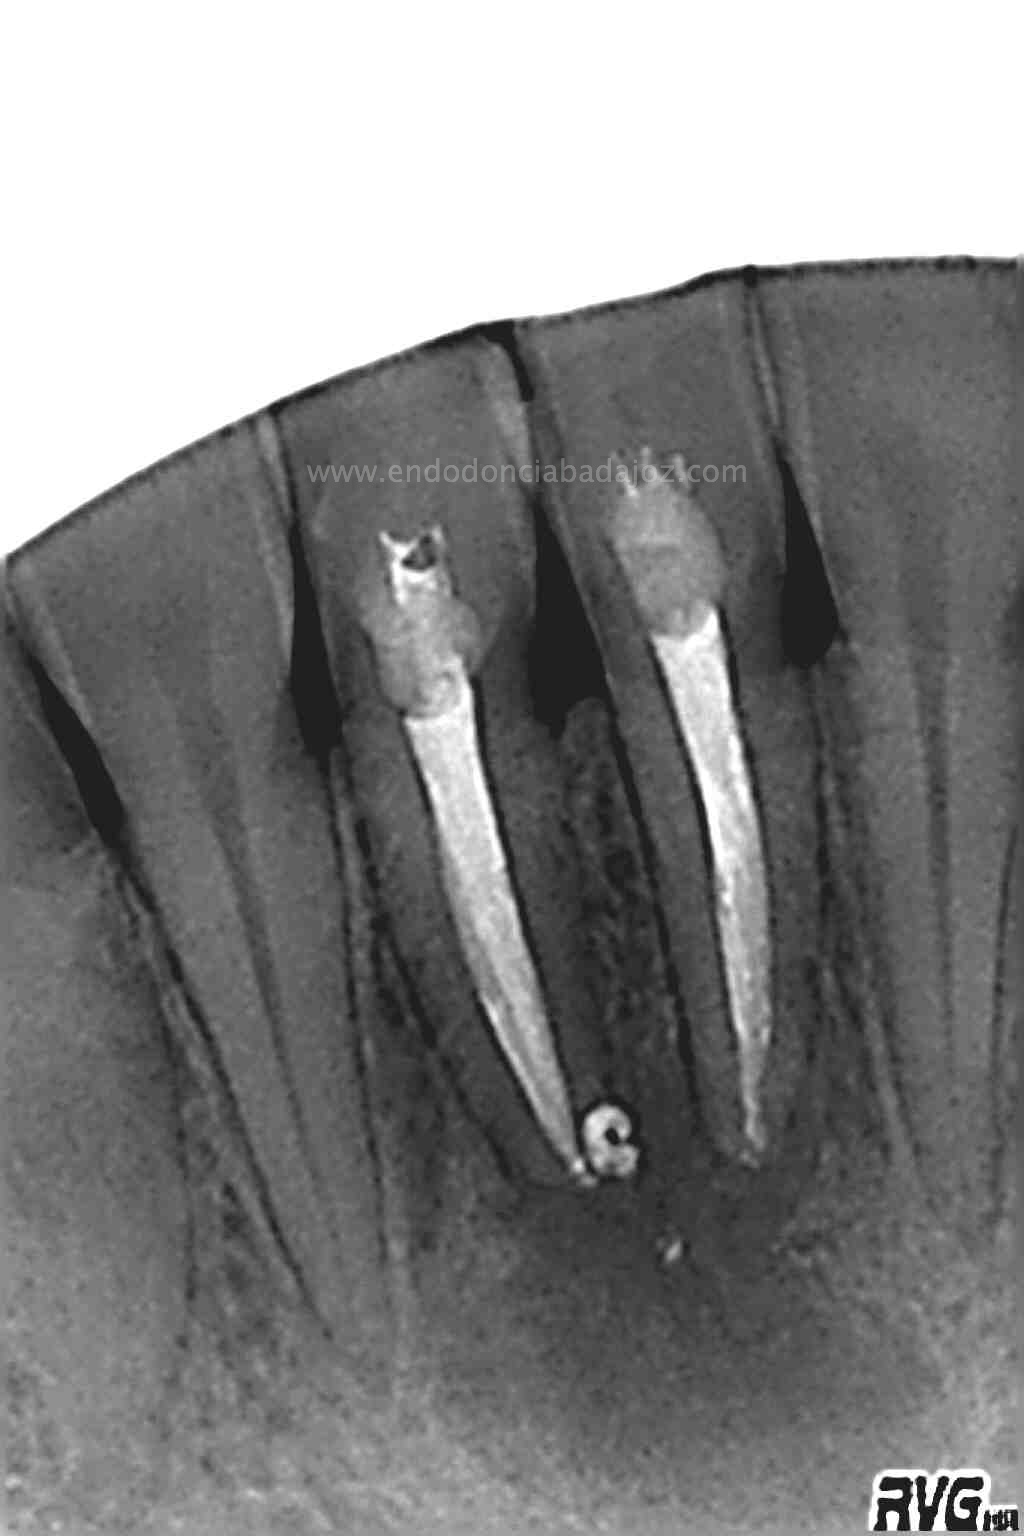

Se le volvió a llamar para otra revisión al año y medio para ver como iba evolucionando:

(revisión al año y 6 meses)